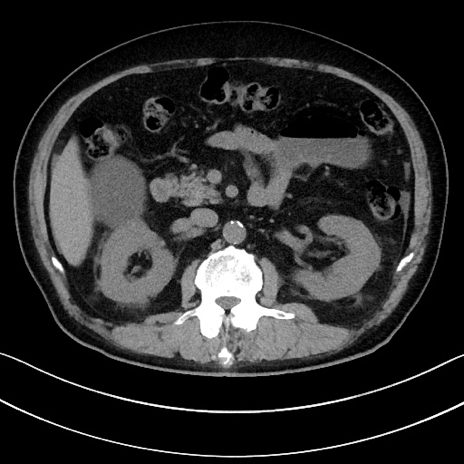

症例15(横断像)

【症例】70歳代男性

【主訴】腹痛

【現病歴】今朝から腹痛あり。全体的に痛い。特に左上の方。排ガスが今日はない。冷や汗が出る。

【既往歴】直腸癌術後

【身体所見】左側腹部〜上腹部に圧痛あり。腹膜刺激症状明らかなではない。軽度反跳痛。左下腹部に術後瘢痕あり。

【データ】WBC 7700、CRP 0.02